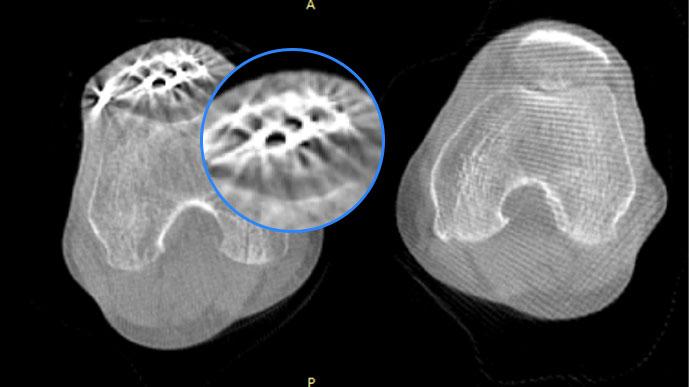

智能金屬偽影抑制算法

關(guān)閉金屬偽影校正

開啟金屬偽影校正